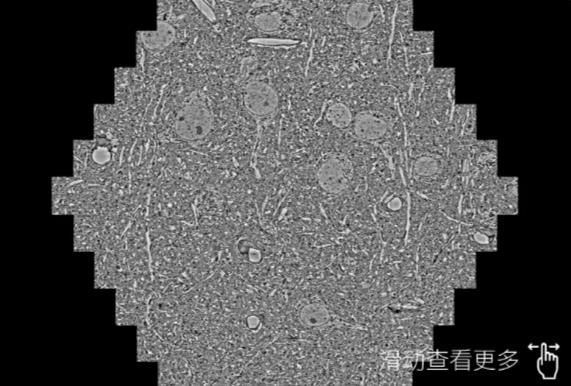

鼠脑切片。左图使用景德镇蔡司景德镇扫描电镜MultiSEM706对165μmx143pm面积区域成像,耗时仅需1.5秒。右图为鼠脑切片中30μm区域放大效果。样品由芝加哥大学B.Kasthuri提供。